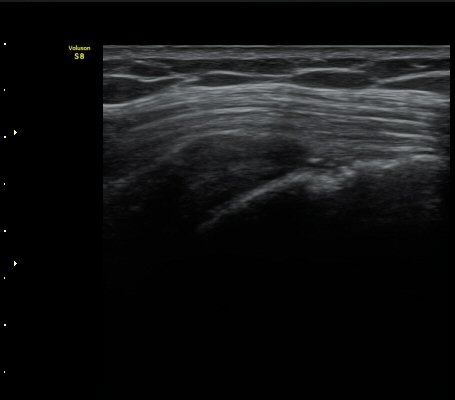

±Ø»ó°Ç Ⱦ´Ü¸é°Ë»ç»ó »ó¿Ï°ñµÎ¸¦ µ¤°í ÀÖ¾î¾ßÇÒ ±Ø»ó°ÇÀÌ º¸ÀÌÁö ¾Ê°í Á¡¾×³¶ÀÌ ÆíÆòÇϰÔ

³»·Á ¾É¾Æ º¸ÀδÙ(±×¸² 3).